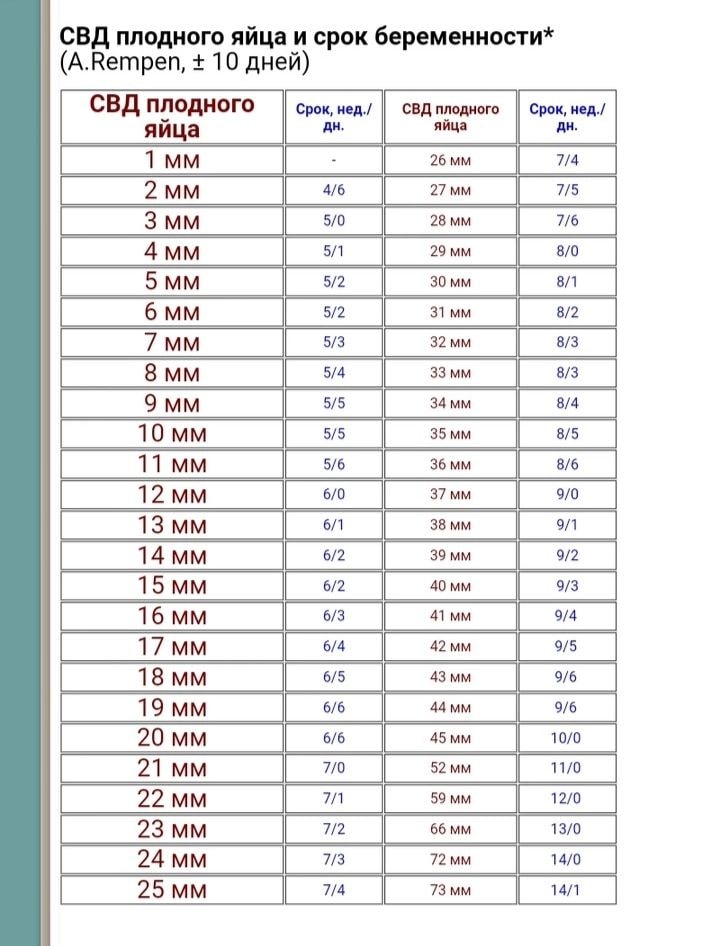

Девочки, добрый день! Кровить перестало, три дня пропила Транексам по 500*3 раза в день + папаверин. Сегодня сходила на УЗИ. Гематом и отслоек нет, свд пя 12 мм, жм 3,6 мм, эмбриона не видно, сб соответственно тоже. Врач сказала погулять еще недельку, потом повторить узи, но не исключила вероятность анэмбрионии. Форма пя тоже вроде как не очень понравилась, либо я неправильно ее поняла. Сказала, что срок по узи и подсадке совпадает - 6,1, и эмбрион уже должен быть :(( Настроение ниже плинтуса - прошлая попытка ЗБ на 8 неделях, теперь это :(( Есть еще шанс на благополучный исход?